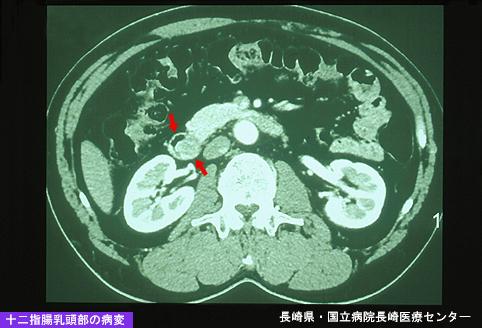

위 GIST를 동반한 비교적 조기의 십이지장 유두부암(증례제시:나가사키현, 국립병원 나가사키의료센터)

[Image-ID:4938]

질환(병리주체)의 분류

악성 상피성종양/선암

부위(장기별)

십이지장/유두부

검사방법

CT

종양의 최대경(밀리미터)

40이상